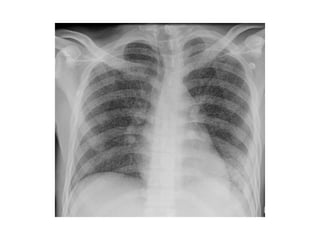

2-Classification :

-May be classified on a chest radiograph into 5

stages :

Stage 0 : normal chest radiograph

Stage I : hilar or mediastinal nodal enlargement

only

Stage II : nodal enlargement and parenchymal

disease

Stage III : parenchymal disease only

Stage IV : end-stage lung (pulmonary fibrosis)